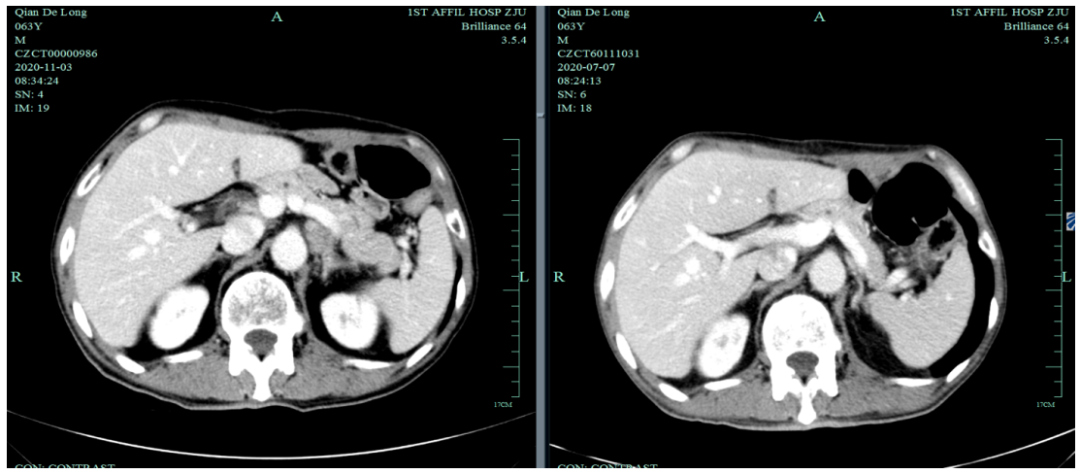

入我院后全面进行评估(2019.4):全腹部CT平扫+增强评估提示腹膜后,胰腺周围多发淋巴结增大,淋巴结转移考虑。

一线化疗疗效评估(2019.6 vs 2019.4):胃癌术后改变。影像评估CR。

2020-11-3全腹部CT平扫+增强提示胃癌术后改变,术周及腹膜后多发肿大淋巴结显示,对照2020-7-7CT淋巴结肿大进展,结合临床疗效评估PD。